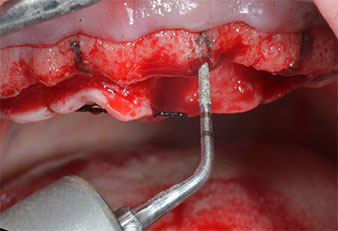

Motor de implantes (Implantmed)

Fig. 5: El diámetro final se logró con los insertos Piezomed I3A/I3P. En el caso de los implantes de 10 mm de las posiciones 11 y 21, los sitios se finalizaron con una fresa rotatoria de 3,5 mm en un motor de implantes (Implantmed).

Debido al hueso relativamente duro (D2) existente en el sector anterior, los sitios de los implantes largos de 10 mm de las posiciones 11 y 21 se finalizaron con una fresa rotatoria de 4 mm de diámetro, en combinación con un contra-ángulo quirúrgico WS-75 L de W&H, el motor de implantes Implantmed de W&H y el módulo opcional Osstell ISQ de W&H. En cambio, debido a la existencia de hueso blando, los sitios posteriores se prepararon hasta un diámetro final de 3 mm utilizando el inserto Piezomed I3P. Por último, los implantes se colocaron a nivel crestal para su osteointegración durante tres meses (figuras 6-10). La prótesis existente se mantuvo sobre cuatro implantes provisionales (figura 8).